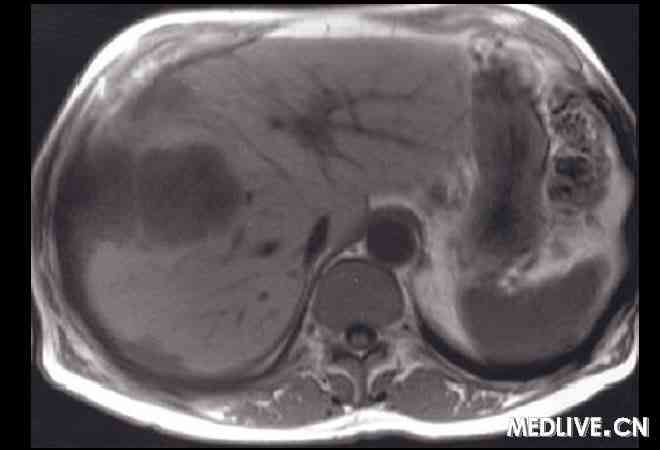

例_读片会_男,57岁,腹痛,消化不良,体重下降。

660x450 - 15KB - JPEG